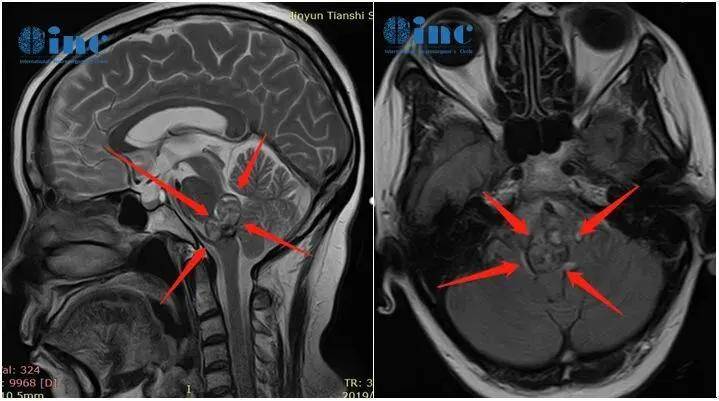

时间回溯至2013年,当时的黄女士因颈椎不适接受核磁共振检查,最初仅被认为是普通颈椎问题,但检查结果却令人震惊:颈椎未见异常,问题在于延髓存在占位性病变,考虑为海绵状血管瘤。

从事医疗行业的她,深知延髓并非普通解剖部位,但由于当时未出现其他明显临床症状,这份诊断报告暂时被搁置。

直至2016年10月初,黄女士开始出现头晕与手指发麻的临床症状。她立即就医,神经外科主任审阅其病史与影像资料后表示:“病灶所处位置极为凶险,位于脑干延髓右侧腹侧面,手术风险极高,可能导致瘫痪、植物人状态甚至死亡,因此建议采取保守治疗。或许现阶段进行手术,效果还不如维持当前状态”。别无选择,黄女士及其家人只能接受保守治疗方案,这虽是当时唯一可行的选择,却也为此后的病情危机埋下隐患。

在保守治疗期间,黄女士始终心怀担忧,而最担心的情况终究发生了。2018年,从1月1日至2月28日,不到两个月时间内,病灶接连发生三次出血,病情急剧恶化。